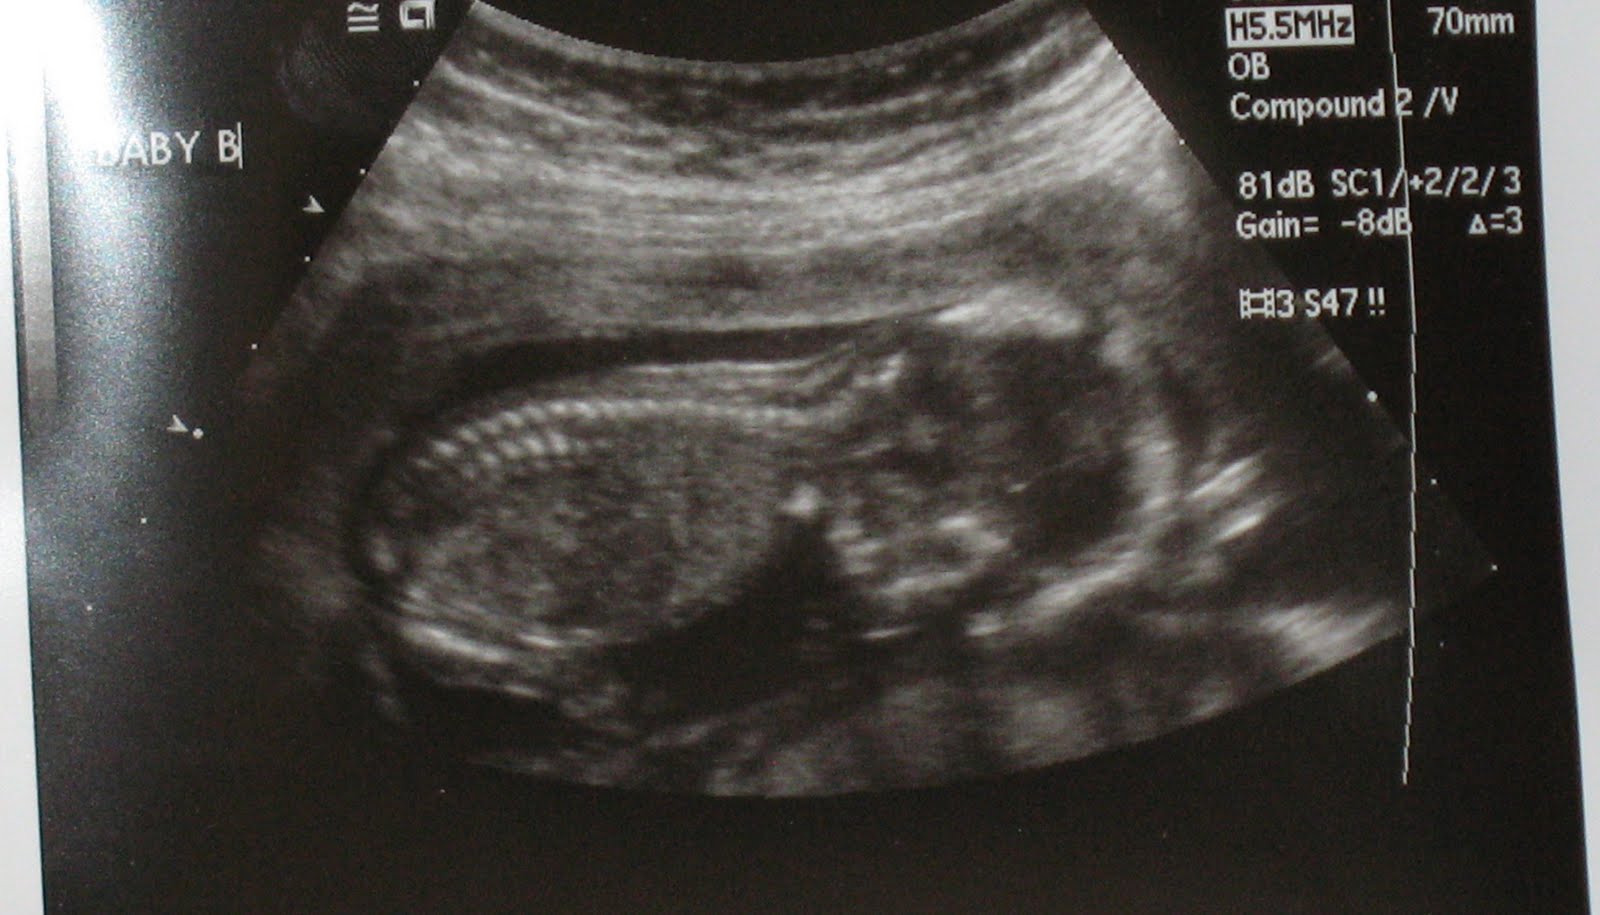

Fetal Spine Ultrasound Normal Vs Abnormal Image Appearances Spinal What Patient Position Is Required For An Infant Spine Sonogram The procedure is performed by using. The procedure is performed by using. Us is the imaging modality of choice for evaluation of the spinal canal in newborns and infants. The examination should be performed with the infant lying in the prone position, although the study can also be done with the patient lying on. If visualization is obscured by patient. What Patient Position Is Required For An Infant Spine Sonogram.

Fetal Spine Ultrasound What Patient Position Is Required For An Infant Spine Sonogram Us is the imaging modality of choice for evaluation of the spinal canal in newborns and infants. The procedure is performed by using. The procedure is performed by using. The examination should be performed with the infant lying in the prone position, although the study can also be done with the patient lying on. If visualization is obscured by patient. What Patient Position Is Required For An Infant Spine Sonogram.